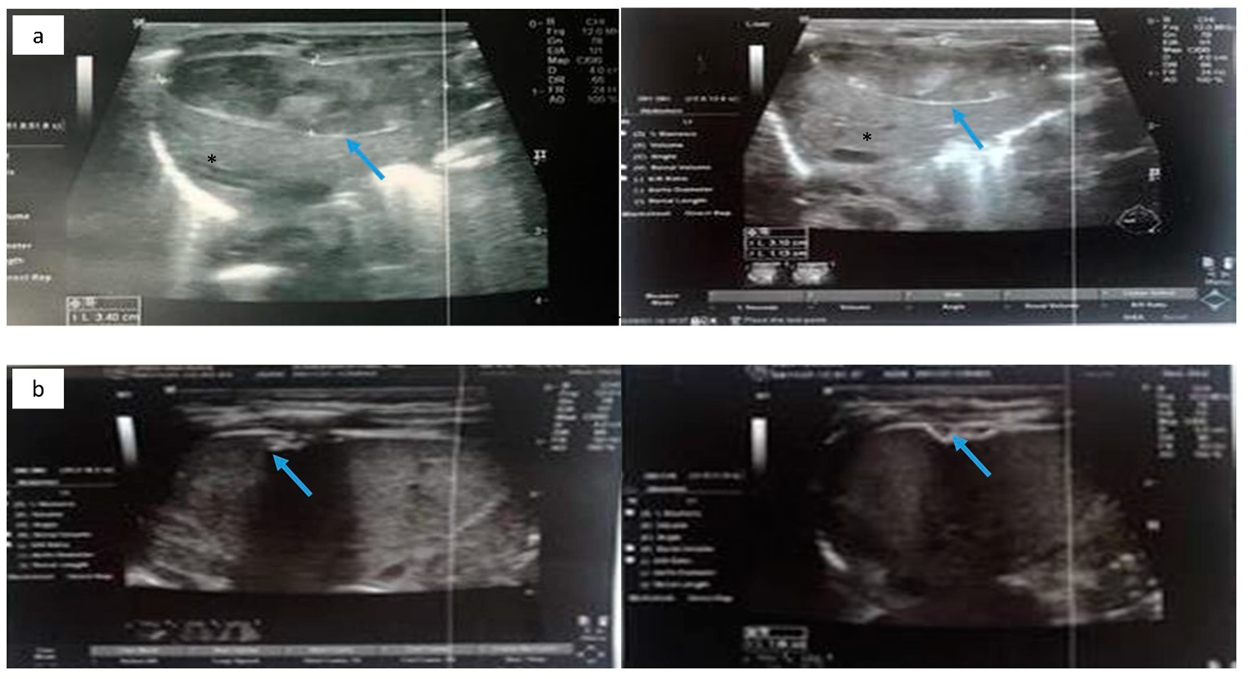

Cranial ultrasound revealed a 1st-degree IVH. Abdominal ultrasound revealed free perihepatic, perisplenic, and inter-intestinal fluid collection (Figure 5a). Abdominal distension was noted in the radiography (Figure 6).

Figure 5.

(a) Free perihepatic fluid collection (blue arrow) in abdominal ultrasound. (b) Abdominal ultrasound depicting subcapsular hematoma of the liver (blue arrow) and hemorrhagic collections in the peritoneal cavity (red arrowhead). Normal liver parenchyma is noted with asterisk (*).

The following day, the clinical condition of the neonate deteriorated, with persistent hypotension, edema and without urine output. A second abdominal ultrasonography revealed subcapsular hematoma of the liver and the spleen and hemorrhagic collections in the peritoneal cavity (Figure 5b). The blood cultures and peritoneal fluid cultures grew Klebsiella pneumoniae. Despite the supportive treatment, the neonate worsened dramatically and deceased on the 8th day.

The neonate was then stabilized, and ultrasonography was performed in order to differentiate the possible causes of blood loss. No IVH was confirmed by cranial ultrasonography, while abdominal ultrasonography depicted a hypoechogenic intrahepatic irregular lesion on the right lobe (3.4 cm × 1 cm) (Figure 8a), with hematoma being the possible diagnosis from the radiologist. Chest and abdominal radiography (Figure 9a) showed an abnormal position of UVC, so it was removed. On the following radiography (Figure 9b) air in the branches of right portal vein and hepatic parenchyma was noted (as shown in Figure 9b).

Figure 8.

(a) Abdominal ultrasonography depicting hypoechogenic intrahepatic irregular lesion on the right lobe (3.4 cm × 1 cm) (blue arrow); and (b) abdominal ultrasonography depicting the calcific deposits (1 cm × 1 cm) (blue arrow) at the right lobe of the liver. Normal liver parenchyma is noted with asterisk (*).